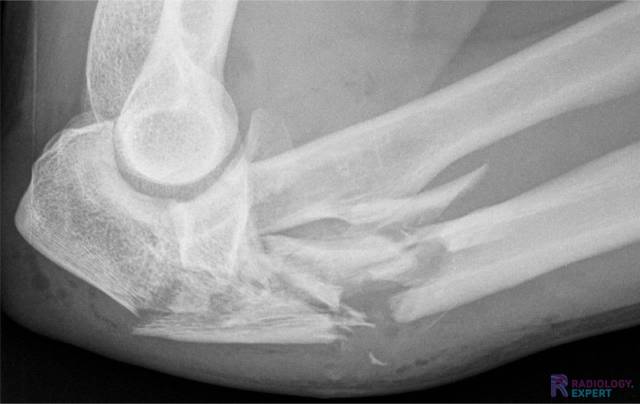

Het detecteren en beschrijven van fracturen lijkt op het eerste gezicht misschien simpel—er is een fractuur, punt. Maar, achter elke fractuur schuilt een samenspel van anatomie, biomechanica, genezing en beeldvorming.

Het herkennen en correct beschrijven van fracturen is voor beginnende artsen en studenten vaak een uitdaging. Fractuurlijnen kunnen subtiel zijn, projecties misleidend en mimics kunnen verraderlijk echt lijken. Een nauwkeurige beoordeling en beschrijving van fracturen is echter essentieel voor het starten van de juiste behandeling én voor het inschatten van complicatierisico’s en prognose.